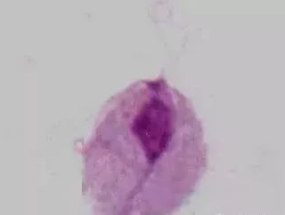

BV是细菌性阴道炎(bacterial vaginosis)的简称,它是加特纳菌和厌氧菌混合感染所导致的阴道内微生态平衡失调,10%~50%的患者...